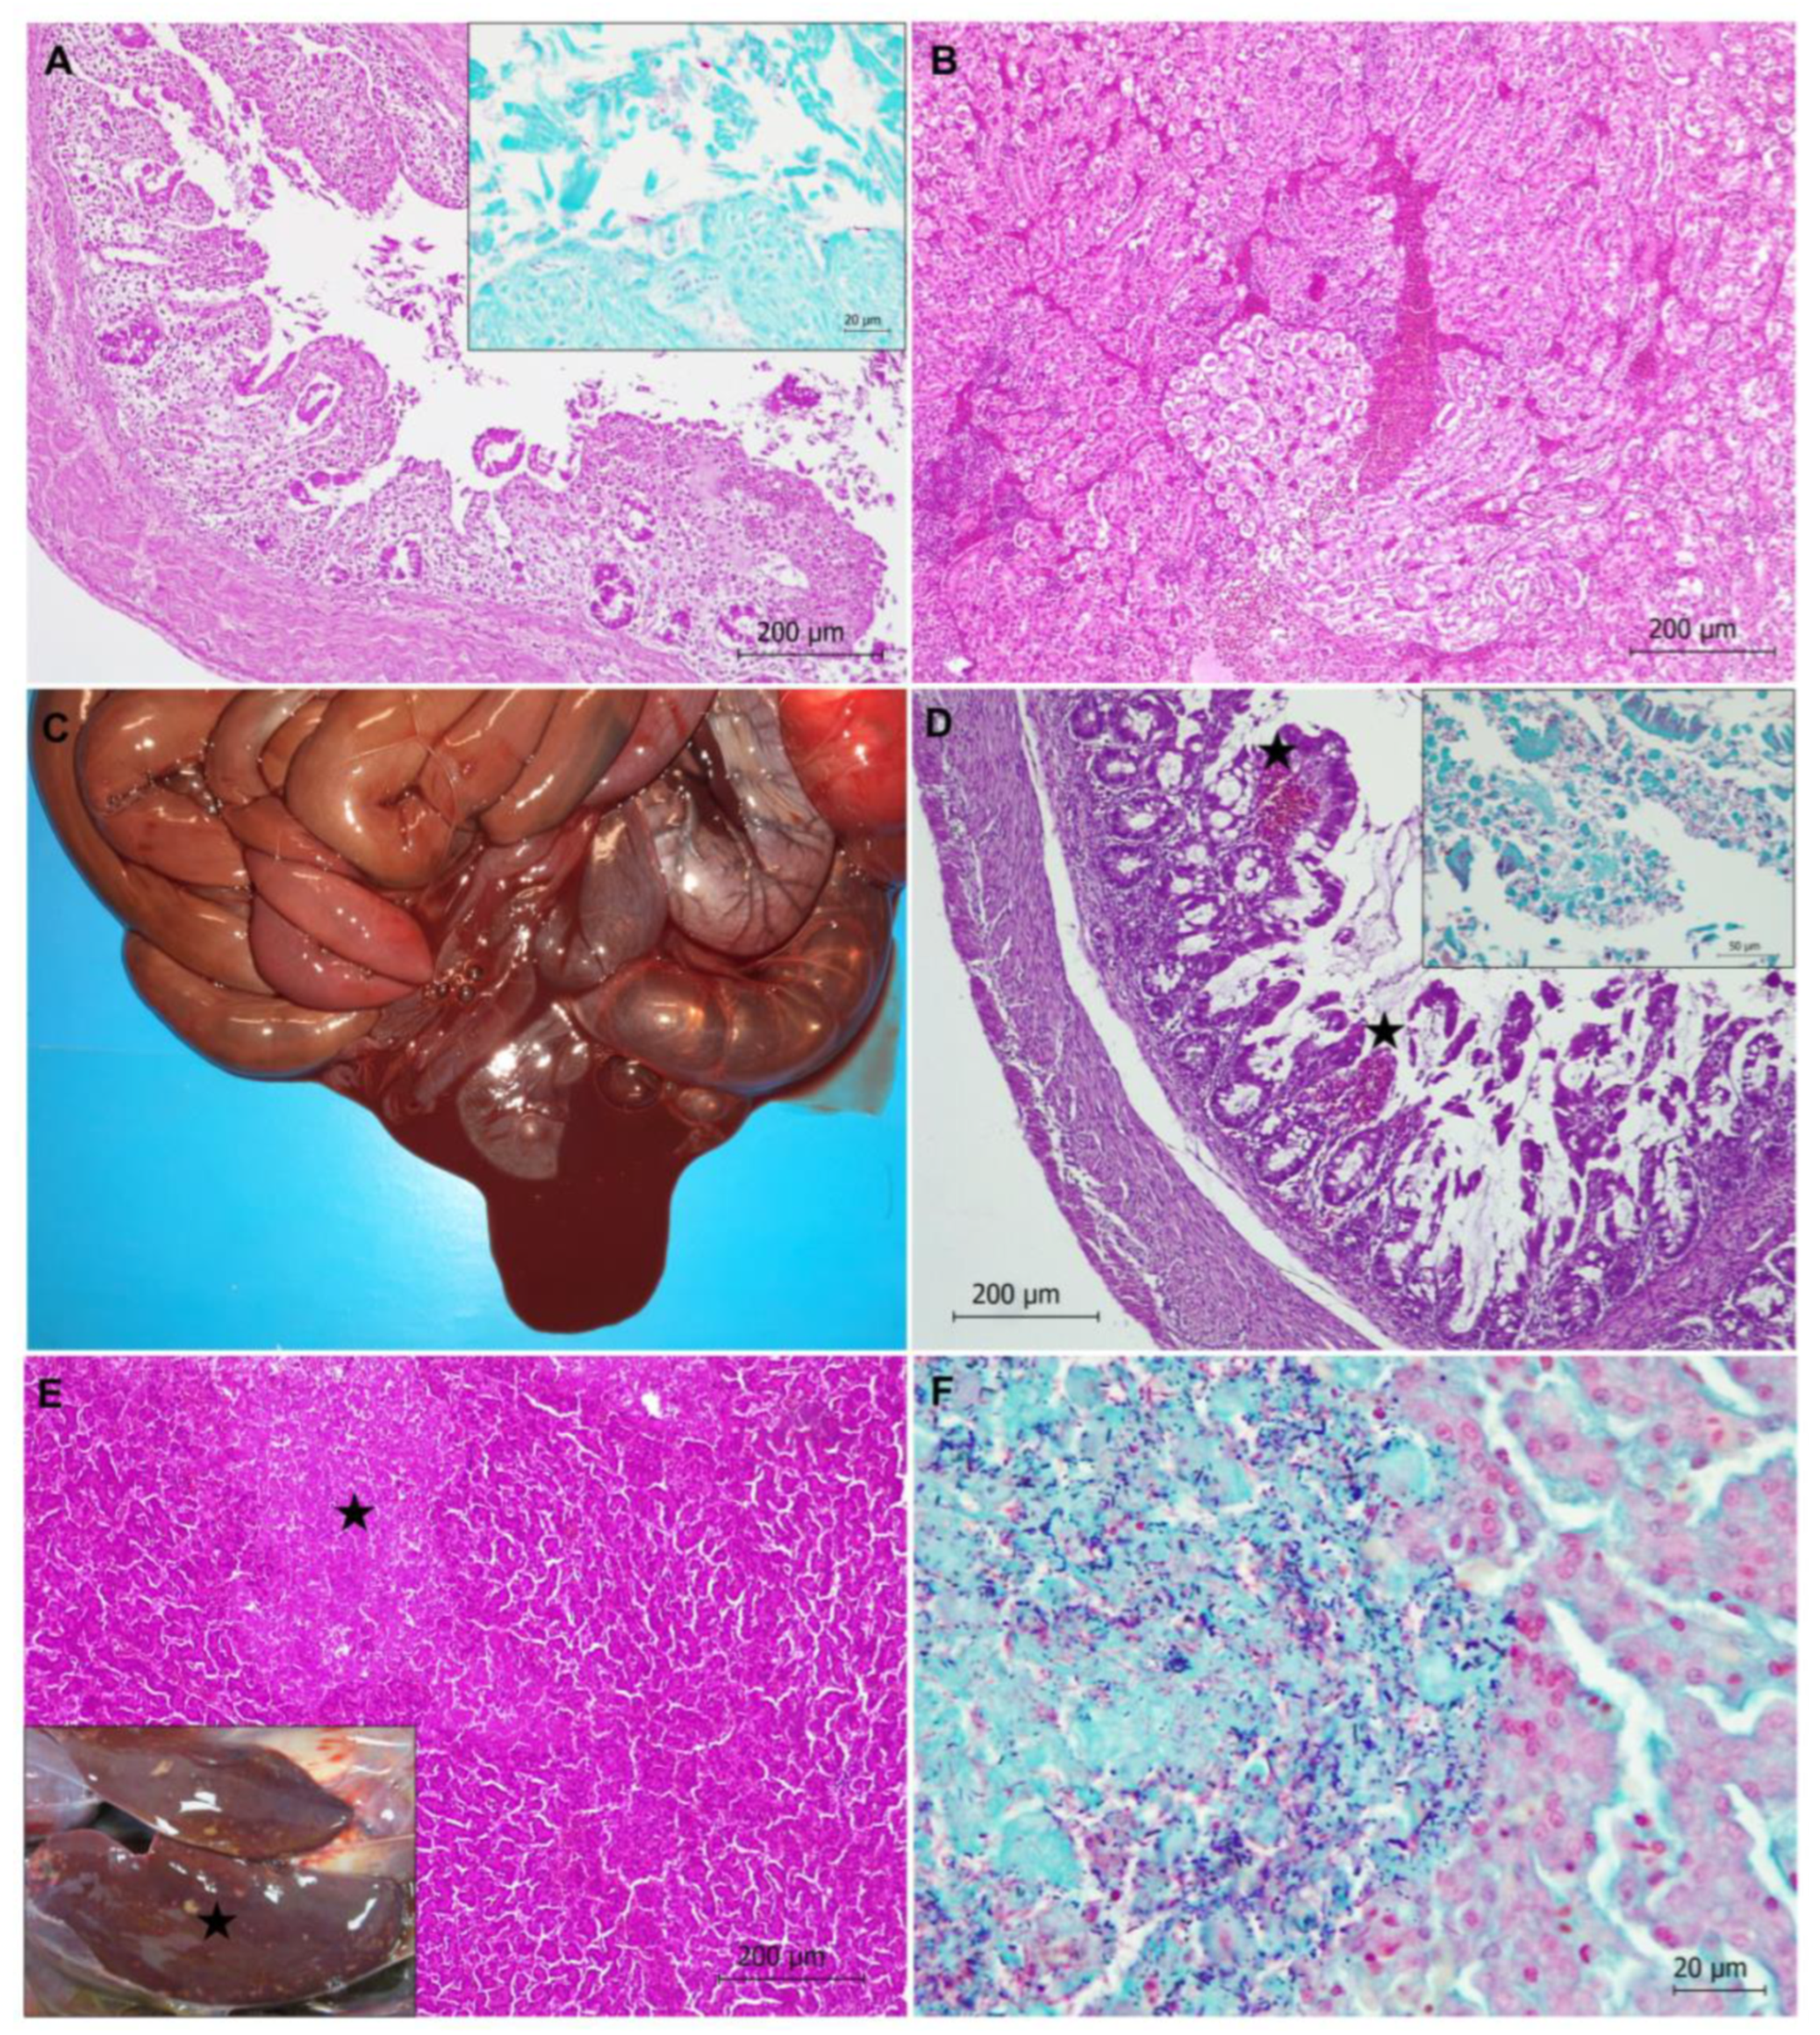

Figure 2.

Colibacillosis (A,B) and clostridiosis (C–F) in Cantabrian capercaillies. (A) Typhlitis due to Escherichia coli infection is observed, characterized by epithelial cell damage of the mucosa and inflammatory infiltrate. Hematoxylin-eosin stain. Inset: Gram-negative bacilli compatible with E. coli are present on the apical surfaces of mucosal epithelial cells. Gram stain. (B) Congestion and hemorrhage in kidney of an animal with colibacillosis. Hematoxylin-eosin stain. (C) Hemorrhagic enteritis is observed in a capercaillie with Clostridium perfringens infection. (D) Histological features in the intestine of a capercaillie with clostridiosis. Necrotic typhlitis is observed; stars indicate hemorrhages. Destruction of intestinal mucosa and network of fibrin are also detected. Hematoxylin-eosin stain. Inset: Presence of numerous Gram-positive bacilli adhered to the mucosal epithelium are shown. Gram stain. (E) Necrotic hepatitis with a focus of necrosis (star) in the liver parenchyma is observed. Hematoxylin-eosin stain. Inset: Multiple whitish-yellowish foci of necrosis (star) are observed in the liver. (F) Numerous Gram-positive bacilli compatible with Clostridium spp. are located in the focus of necrosis observed in (E). Gram stain.

In total, 6 out of the 11 animals with E. coli infection showed acute enteritis, more severe in caeca (typhlitis), with or without impaction. Enteritis was characterized by an inflammatory infiltrate consisting of lymphocytes and macrophages and epithelial cell damage of the mucosa (Figure 2), with microerosions of the mucosa surface. Gram-negative bacilli compatible with E. coli were found on the apical surface of mucosa. The remaining animals with E. coli infection showed septicemia or sacculitis.

One capercaillie showed necrotic hemorrhagic enteritis due to C. perfringens bacterium (Figure 2). Diffuse necrosis of the mucosa was observed. Gram-positive bacilli colonization of the tip of the villi with associated hemorrhages and networks of fibrin in the lumen of the intestine (mainly in caeca) were also noticed (Figure 2).

Three capercaillies showed necrotic hepatitis (Figure 2). Well-demarcated multi-focal necrosis was observed in the liver parenchyma without an associated inflammatory infiltrate. Gram staining revealed clumps of bacilli morphologically compatible with Clostridium spp. in the pale, amorphous necrotic parenchyma (Figure 2). In one case, C. perfringens was identified via microbiology. One of these animals showed neurological clinical signs compatible with hepatic encephalopathy.